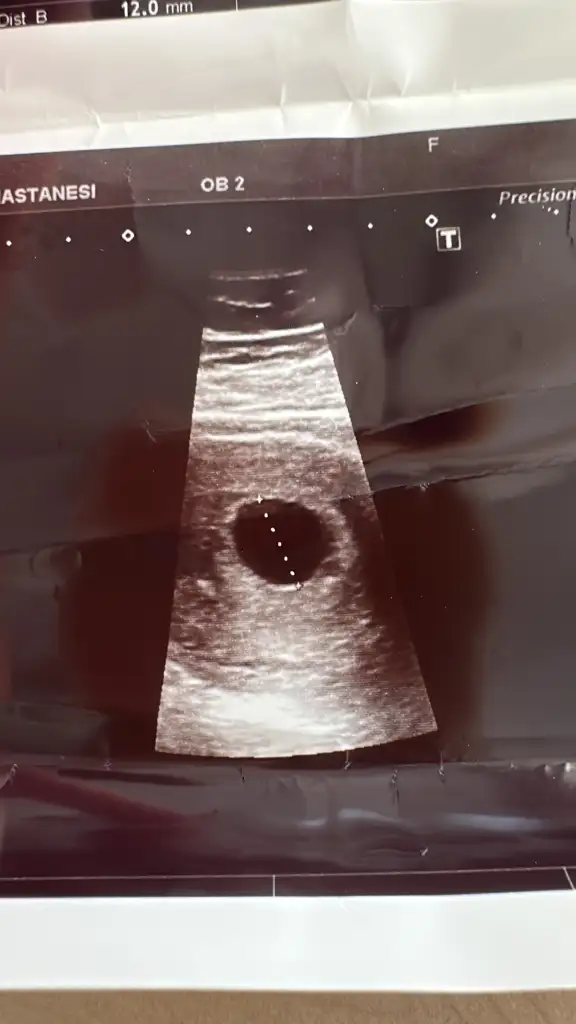

6+3 haftalıkken doktora kontrole gittim. Kese haftasıyla uyumlu ama bebek görünmüyor kese boş dedi. Keseyi ben de gördüm içi boştu. 2 hafta bekleyelim dedi. Şuan 7+3 tüm hamilelik belirtileri var ama korkuyorum acaba boş gebelik mi yoksa sonradan görünür mü? Bu durumu yaşayan var mı aranızda

Merhaba size bişey sorabilir miyim? Kuzenim 7+2 haftalık hamile fakat keseyi gördüler içi boş daha erken mi acaba normal mi bu durum

Kesenin içi boş dedi doktor 6. Haftadayım ovulasyon takibiyle 26 temmuzda yumurtlama gördüm ama kürtaj olmam gerektiğini söylüyoe doktor sizce nasıl yol izlemem gerekiyor